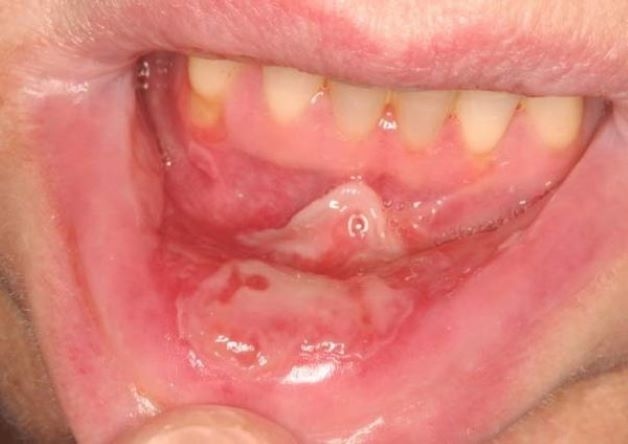

Hình ảnh tế nào niêm mạc miệng

Dù ở các mức độ khác nhau, nhưng loét niêm mạc ở miệng đều có đặc điểm chung là có màu đỏ xung quanh, trung tâm có mảng màu vàng, gây cảm giác đau đớn trong 2 – 3 ngày đầu, bệnh sẽ giảm đau khi vết thương bắt đầu lành dần.

Loét niêm mạc miệng đều có đặc điểm chung là có màu đỏ xung quanh, trung tâm có mảng màu vàng, gây cảm giác đau đớn trong 2 – 3 ngày đầu